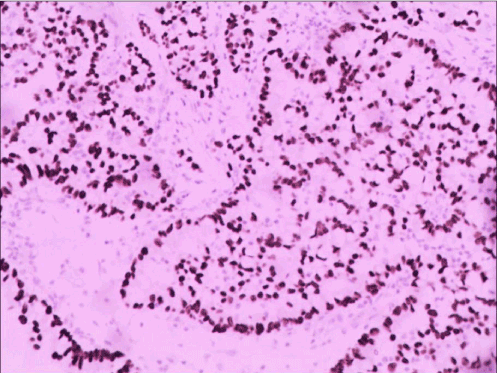

Because of the high FDG uptake in gray matter, the contrast of the uptake from the tumor versus normal brain tissue decreases, leading to low sensitivity. It is accepted that the correlation of grades with 18F-FDG showed high-grade brain tumor  demonstrated hypermetabolism with high FDG uptake, while low-grade brain tumors revealed low levels of glucose metabolism with less than, equal to, or slightly higher than that of white matter. Cerebral metastases mainly occur in the supratentorial (80%) and characterized by significant cerebral edema. As for this case, the edema is slightly both from MR and CT brain scan, and the FDG uptake is deficient completely, and the patient was wrongly regarded as low-grade gliomas initially, and lung cancer in right upper lobe was highly suspicious. Then surgical resection was undertaken to remove the lesion in the right frontal lobe, and the pathology diagnosis was metastatic adenocarcinoma (Figure 4 A-D). The case was finally conformed cerebral metastasis from NSCLC, and the slightly higher CEA also aided the diagnosis.

Figure 4a. HE staining: Microscopic examination of brain tumor lesion shows tumor cells with tubular formation, nuclear enlargement, nuclear fission, which suggest metastatic brain tumor.

Figure 4b. HE staining: Microscopic examination of brain tumor lesion shows tumor cells with tubular formation, nuclear enlargement, nuclear fission, which suggest metastatic brain tumor.

Figure 4c. Immunohistochemical staining: TTF-1(+), CK8-18(+).

Figure 4d. Which suggest the brain metastasis originates from lung adenocarcinoma.